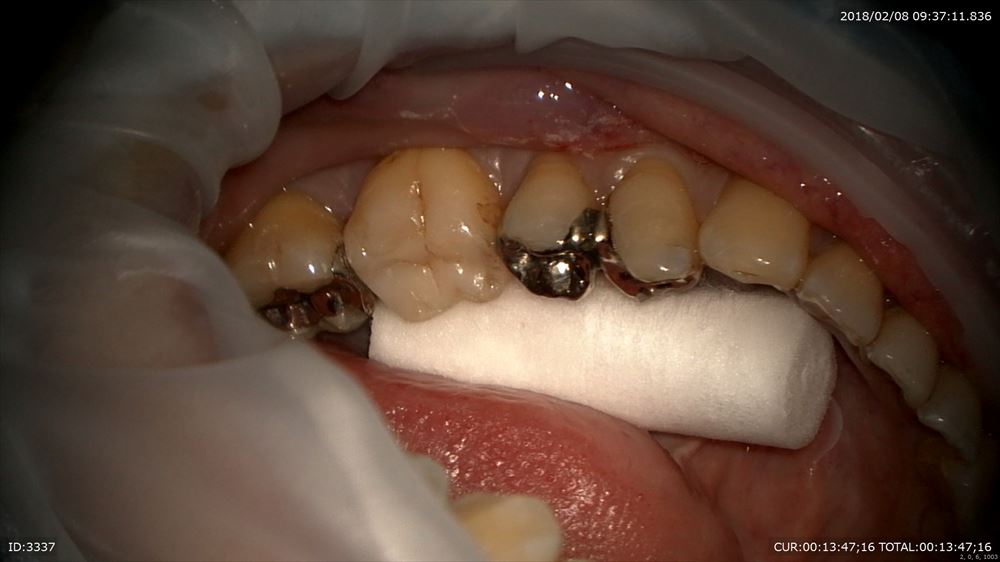

左下

詰め物をオーダーメイド

フィット

このように隙間がなく細菌の侵入を防ぎます。

とにかくやり直しのない治療を目指す為に当院では金属を使用しません。